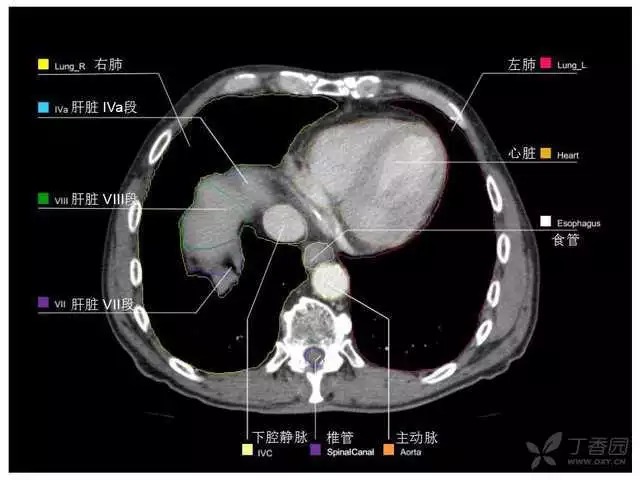

腹部肝脏高清CT断层的图谱

全腹部高清CT图谱,淋巴结彩色图谱,血管解剖图谱大汇总!

超声肝脏分叶及分段

肝脏分段和基本解剖学标志